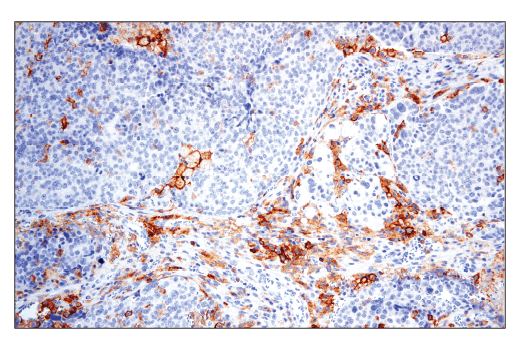

W, IHC-Bond, IHC-P, IF-IC

W: Western Blotting IHC-Bond: IHC Leica Bond IHC-P: Immunohistochemistry (Paraffin) IF-IC: Immunofluorescence (Immunocytochemistry)